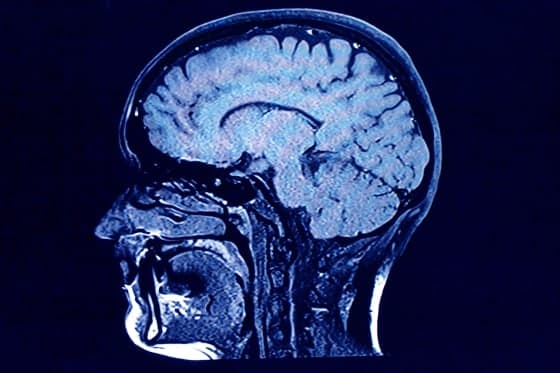

Para estudiar estas transiciones, usaron imágenes de difusión (dMRI) de aproximadamente 3.800 personas, desde recién nacidos hasta los 90 años. Infirieron vías neuronales a partir del movimiento de moléculas de agua a lo largo de fibras mielinizadas. Con esos datos, modelaron el fortalecimiento y el debilitamiento de la red cerebral promedio a nivel global.